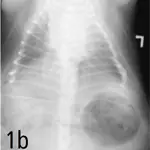

Radiographs. Survey radiographs of the thorax (Figure 1) demonstrate morbid obesity. No significant abnormalities are noted in the lung fields, although assessment is difficult due to obesity, thoracic conformation, and poor inspiration. There is variation in the tracheal diameter in the cervical region. The cardiac silhouette is unremarkable.

Right lateral (a) and dorsoventral (b) views of the thorax demonstrating severe obesity and variation in the tracheal diameter in the cervical region. The cardiac silhouette and lung fields are unremarkable.